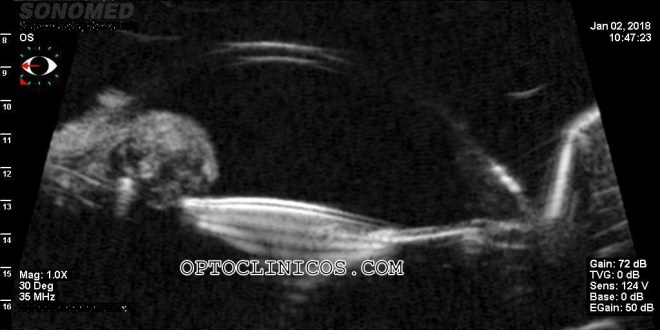

Tercer caso:

Paciente con queratocono. No lleva lentes de contacto, solo gafas con una refracción previa en gafa de:

OD: -4.25-1.75×90 av 0.3 dif

OI: -4.25-0.50×100 av 0.6 dif

Nos piden valoración del potencial de agudeza visual y así pensar en la mejor indicación de tratamiento.

Se le prueban lentes de contacto semiesclerales y refracción encima, con lo que conseguimos una agudeza visual en el ojo derecho de 0.9 y en el ojo izquierdo de 1.0 difícil.

Debido al alto potencial de agudeza visual presentado, se programa cirugía de anillos en ambos ojos.